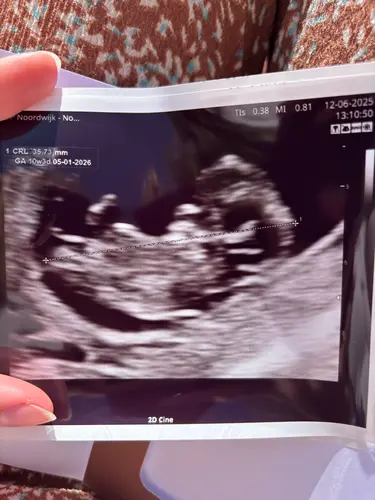

Gisteren de termijnecho gehad met 10+3. En sindsdien heel sterk het gevoel dat het een meisje is.

- ik ben veel misselijker dan bij mijn zoontje

- ik heb vannacht gedroomd dat het een meisje is

- nub en skull theorie zeggen iets grotere kans op meisje, maar is nog een beetje te vroeg met 10+3 (via chat gpt)

Ik heb gewoon het gevoel opeens heel sterk. Met ons zoontje had ik ook na de echo opeens heel sterk het gevoel dat het een jongen was.